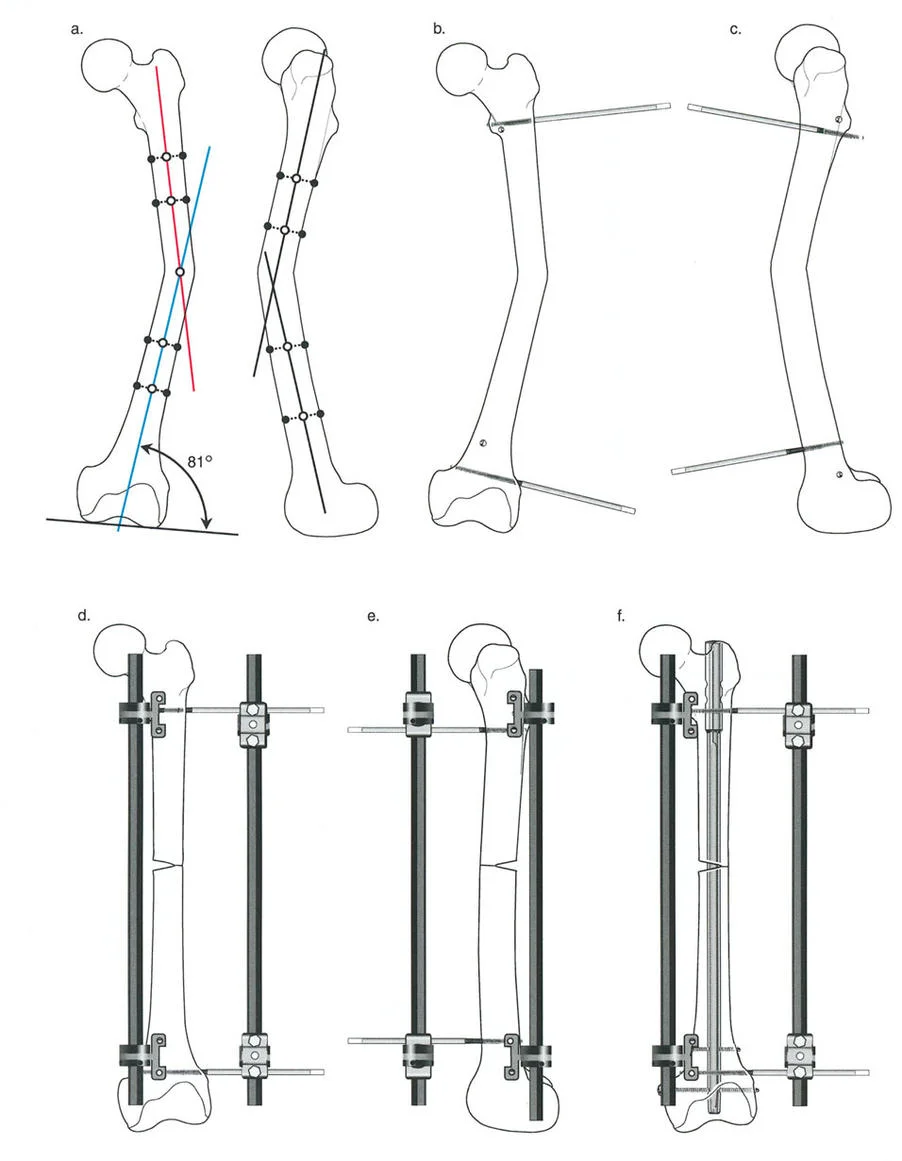

تثبيت المسمار الداخلي بمساعدة المثبت الخارجي (FAN) هو تقنية جراحية حديثة تجمع بين دقة المثبت الخارجي المؤقت واستقرار المسمار الداخلي الدائم، مما يوفر تصحيحًا فائقًا لتشوهات العظام المعقدة مع راحة فورية للمريض وتعافٍ أسرع.

الخلاصة الطبية السريعة: تثبيت المسمار الداخلي بمساعدة المثبت الخارجي (FAN) هو تقنية جراحية حديثة تجمع بين دقة المثبت الخارجي المؤقت واستقرار المسمار الداخلي الدائم، مما يوفر تصحيحًا فائقًا لتشوهات العظام المعقدة مع راحة فورية للمريض وتعافٍ أسرع.